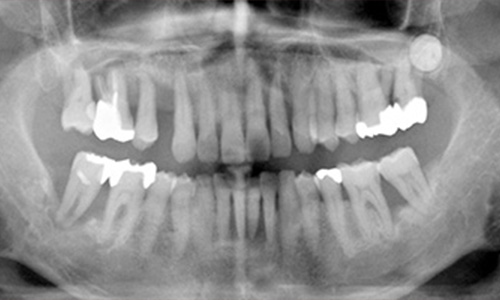

レントゲン写真では歯根の先端まで歯槽骨の吸収が進行しているのがわかります。特に大臼歯部はほとんど歯槽骨の支えがありません。歯槽骨の頂点に線を引いていますが、線はさらに波をうったような状態になっています。